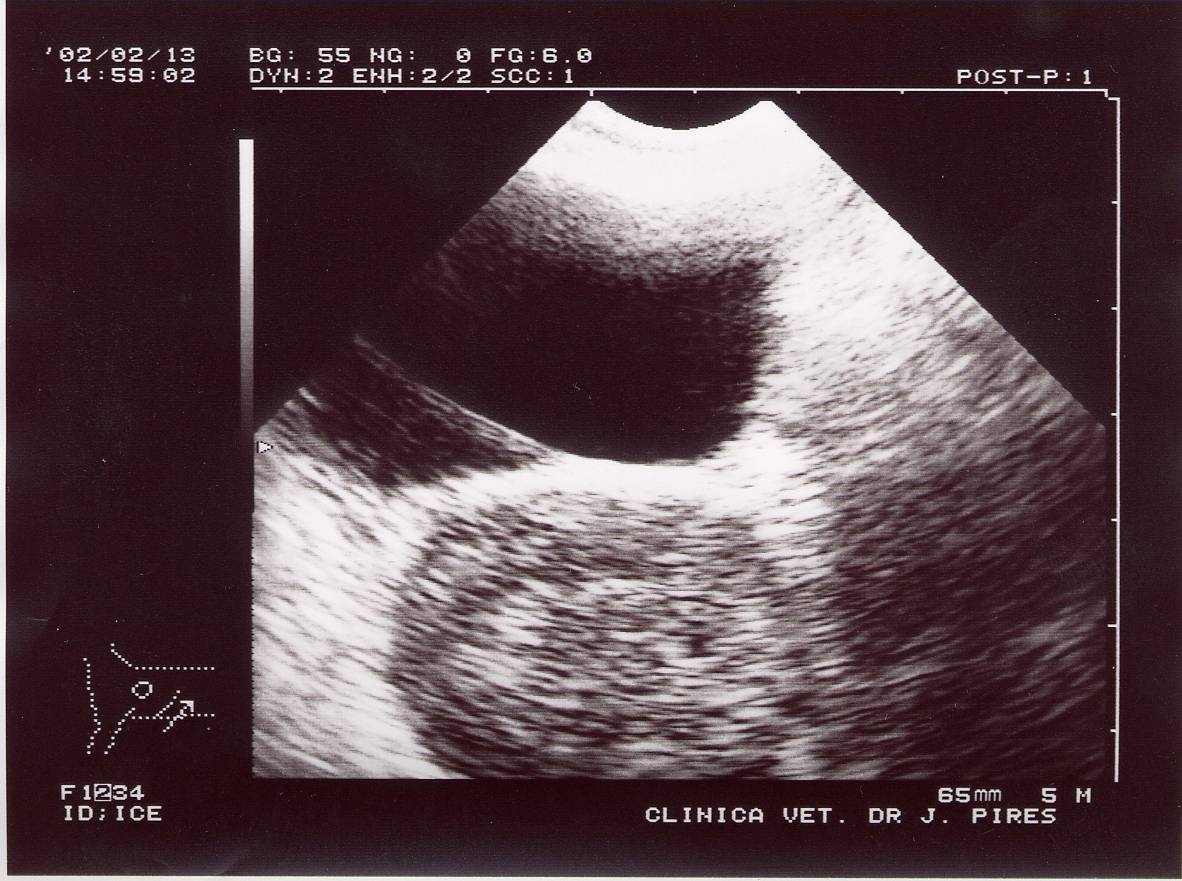

Ecografia: Imagens hiperecogénicas que evidenciam hipertrofia dos gânglios inguinais profundos.